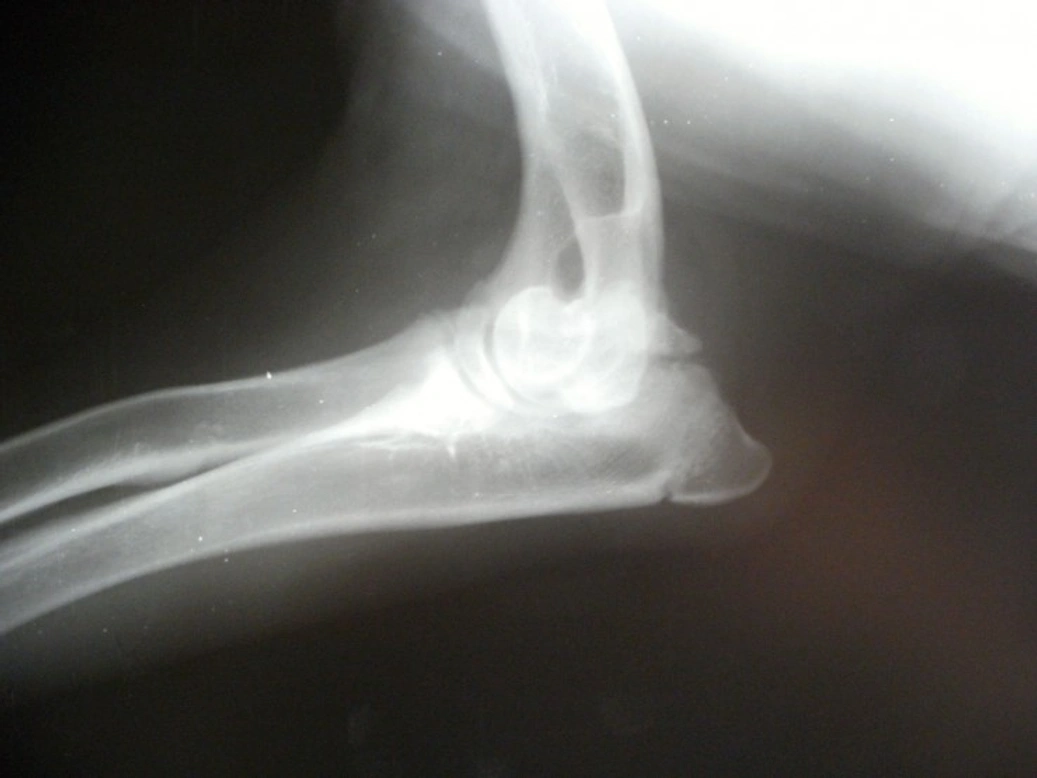

The primary testing method involves taking X-rays of the dog's elbows, which are assessed by specialists who assign a score from 0 to 3. A score of 0 means clear elbows, and 3 indicates severe dysplasia. If a dog’s elbows have different scores, the higher score is the one considered for breeding suitability.

Veterinarians may also carry out physical examinations to localise pain and assess lameness. If further detail is needed, advanced imaging such as CT scans can reveal more about bone and soft tissue health, especially if X-rays are inconclusive. In some cases, arthroscopy—a minimally invasive surgical procedure—allows direct visualisation of the joint and can help with both diagnosis and treatment during the same operation.